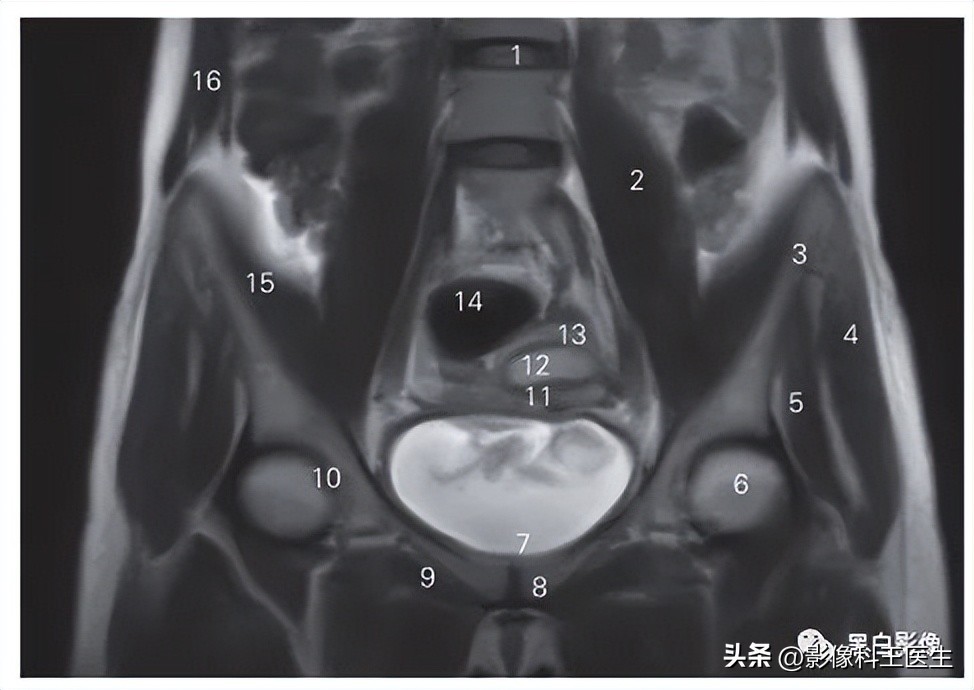

女性盆部与会阴MR冠状断层T2加权图像

图8-1 经耻骨联合和膀胱的冠状断层MR T2加权图像

1 腹主动脉 abdominal aorta 2 左髂总动脉 left common iliac artery

3 髂肌 iliacus 4 臀中肌 gluteus medius

5 臀小肌 gluteus minimus 6 膀胱 urinary bladder

7 耻骨联合 pubic symphysis 8 阔筋膜张肌 tensor fasciae latae

9 耻骨支 pubic ramus 10 乙状结肠 sigmoid colon

11 髂骨翼 iliac ala 12 升结肠 ascending colon

13 腹外斜肌 obliquus externus abdominis

图8-2 经髋关节前份和子宫的冠状断层MR T2加权图像

1 第3腰椎间盘 3th lumber intervertebral disc 2 腰大肌 psoas major

3 髂嵴 crisla iliaca 4 臀中肌 gluteus medius

5 臀小肌 gluteus minimus 6 股骨头 head of femur

7 膀胱 urinary bladder 8 耻骨 pubis

9 闭孔外肌 obturator externus 10 髋臼 acelabulum

11 子宫结合带 uterine junction zone

12 子宫内膜 endometrium of uterus

13 子宫肌层 mesometrium of uterus

14 乙状结肠 sigmoid colon 15 髂肌 iliacus

16 腹外斜肌 obliquus externus abdominis